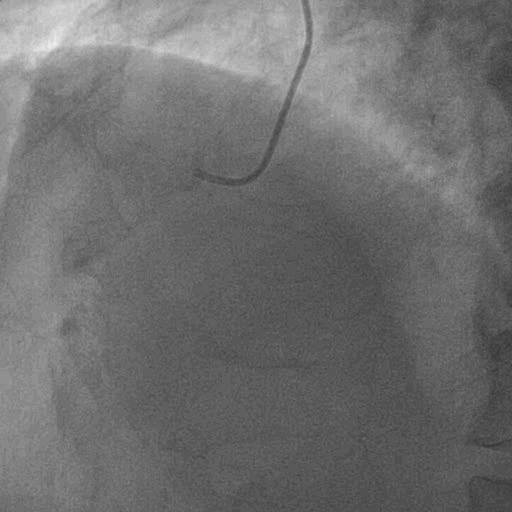

术前造影:

双侧造影: